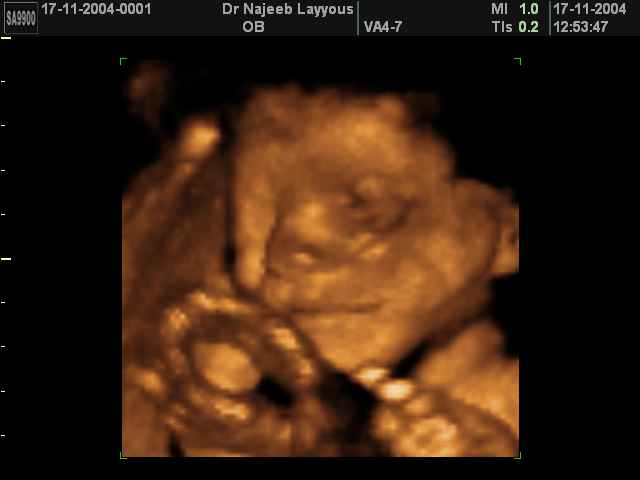

صور لتصرفات الجنين داخل الرحم بجهاز الالتراساوند ثلاثي الأبعاد | الدكتور نجيب ليوس

صور بجهاز الموجات فوق صوتية ثلاثي الأبعاد لتصرفات الجنين داخل الرحم